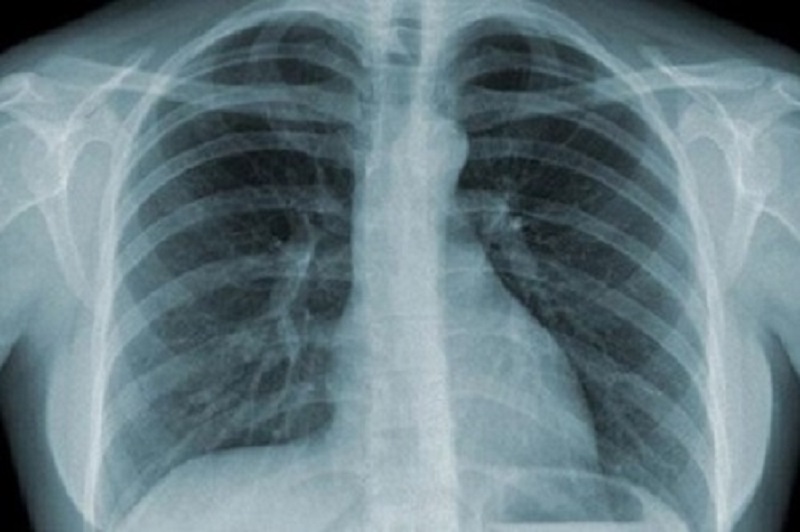

ung-thu-phoi-giai-doan-cuoi-2 Bệnh nhân viêm phổi giai đoạn cuối gặp nhiều vấn đề sức khỏe nghiêm trọng